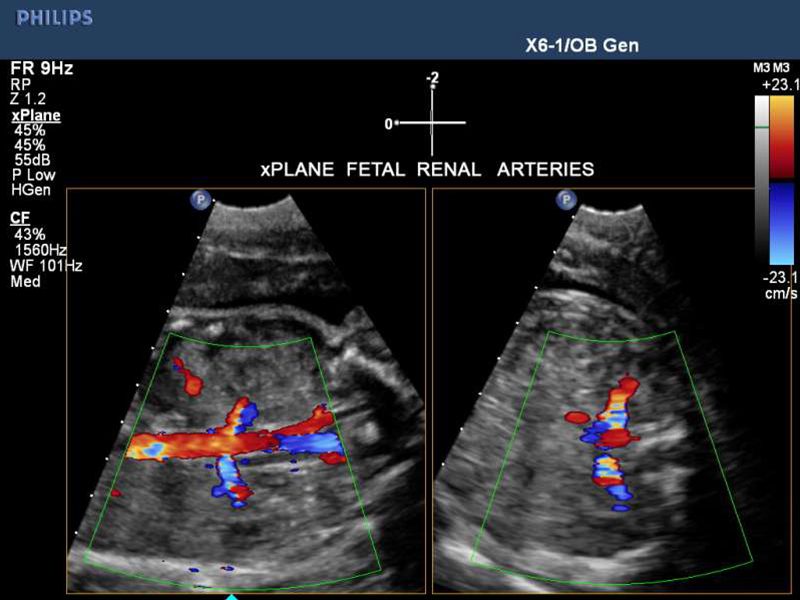

• Como el método preferido de obtención de imágenes para el monitoreo de una mujer embarazada y su hijo que aún no ha nacido.

Ultrasonido gineco obstétrico

Ultrasonidos obstétricos 3D - 4D

Ultrasonido doppler